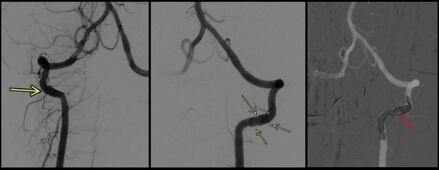

Case Summary: In less than 400 words, please summarize the case. Briefly describe the case and any particular complexities and/or complications encountered.: A 5-year-old boy with no past medical history presented to the emergency department with two weeks of right-sided headaches and fatigue followed by acute onset right-sided weakness and ataxic gait starting 23 hours before arrival. Two months prior, he was hit in the back of the head by a wakeboard at a lake without loss of consciousness or other symptoms. He continued to participate in water sports that day without issue. On the day of presentation, National Institutes of Health Stroke Scale (NIHSS) score was 4 for partial right hemianopia, right facial palsy, right arm drift, and mild dysarthria. Initial head and neck computed tomography (CT) demonstrated infarcts involving bilateral posterior cerebral artery (PCA) territories. There were luminal irregularities of the distal V2 and V3 segments of the left greater than right vertebral arteries (Figure 1), with narrowing of the left vertebral artery below the lateral mass of C1. Anticoagulation with heparin was started on hospital day 2.